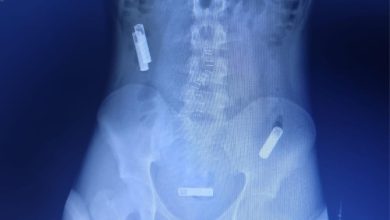

مستشفى النور التخصصي يُنقذ حياة مريض نفسي ابتلع 3 بطاريات ريموت تليفزيون

نجح فريق طبي بقسم المناظير والجهاز الهضمي بمستشفى النور التخصصي من استخراج ٣ بطاريات ريمون تلفزيون من بطن مريض نفسي…